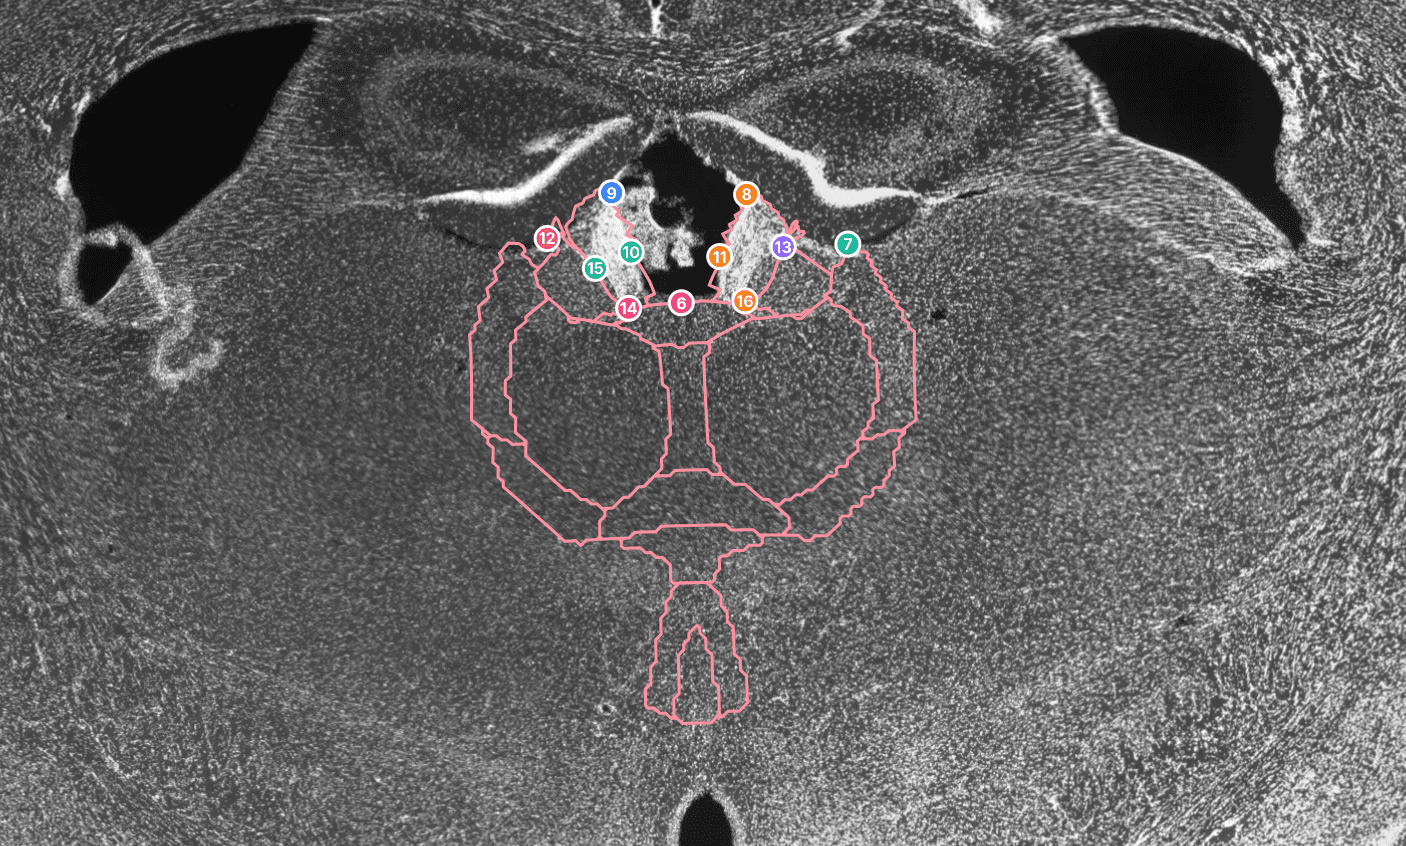

Automated mouse brain atlas registration from a single 4x DAPI overview with precise 10x or 20x detail-image alignment.

NeuroQP turns one 4x DAPI whole-slice overview into a complete brain atlas registration that supports your whole study. Your 10x or 20x detail field is then placed on top of the registered 4x slice, and quick manual refinements keep the local alignment accurate. Since the entire atlas is available, you can update brain region selections later without redoing the registration process.